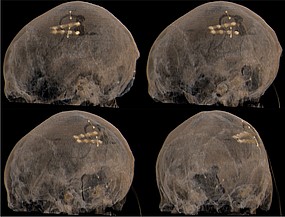

Bei bestimmten Bewegungsstörungen, die nicht oder nicht mehr ausreichend auf eine medikamentöse Therapie ansprechen, ist es möglich, die hierfür verantwortlichen Hirnareale durch die sog. Tiefe Hirnstimulation zu beeinflussen. Hierbei werden feine Elektroden in das Gehirn eingesetzt, um fehlerhafte Nervenstrukturen mit elektrischen Impulsen zu aktivieren oder zu hemmen. Beim Morbus Parkinson, dem essentiellen Tremor oder der Dystonie sind beispielsweise spezifische Hirnareale überaktiv, die dann gezielt durch die Tiefe Hirnstimulation gehemmt und die Symptome wie Zittern oder Muskelsteifigkeit dadurch unterdrückt werden können. Die Hirnregionen selbst bleiben dabei intakt, sodass die Stimulation jederzeit rückgängig gemacht werden kann. Die elektrische Stimulation wird durch einen Impulsgeber gesteuert, der ähnlich wie ein Herzschrittmacher unter die Haut an der Brust der Patient:innen implantiert wird. Die Einstellungen des Impulsgebers lassen sich von außen jederzeit verstellen, sodass die Stimulation an veränderte Bedürfnisse der Patient:innen stets angepasst werden kann.

Neben den Bewegungsstörungen sind mittlerweile auch einige neuropsychiatrische Erkrankungen, wie die Depression oder Zwangsstörungen bekannt, bei denen fehlerhafte Hirnareale durch die Tiefe Hirnstimulation verändert (=moduliert) werden können. Bei schweren therapieresistenten Verläufen kann auch hier dieses Verfahren angeboten werden.

Tiefe Hirnstimulation bei psychiatrischen Erkrankungen

Neben den Bewegungsstörungen sind mittlerweile auch einige neuropsychiatrische Erkrankungen, wie die Depression oder Zwangsstörungen bekannt, bei denen fehlerhafte Hirnareale durch die Tiefe Hirnstimulation verändert (=moduliert) werden können. Gemeinsam mit dem ZI Mannheim erforschen wir neue Zielstrukturen und Indikationen.